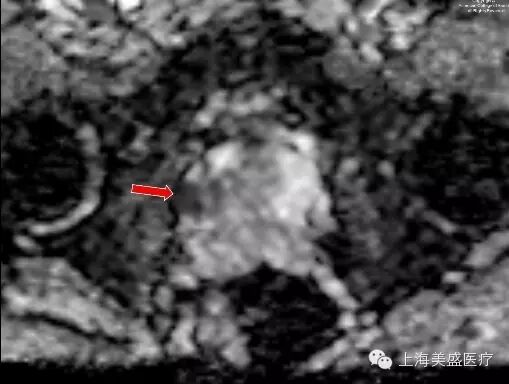

图 3. ADC 示上述异常区域表现为弥散受限(箭头示)